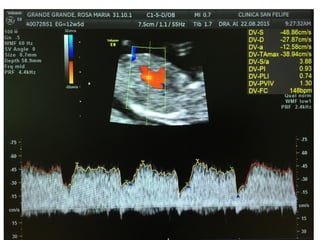

DUCTUS VENOSO

• Vaso pequeño que conecta la vena umbilical con la

proximidad de la aurícula derecha. Tiene un papel crítico

dirigiendo la sangre oxigenada al cerebro fetal

• Un 20% de la sangre oxigenada de la placenta sobrepasa el

hígado y se dirige al corazón fetal. Entra en la aurícula

derecha y luego a la izquierda, a través del foramen oval.

• De la aurícula izquierda pasa al ventrículo izquierdo y luego

a la aorta

DUCTUS VENOSO • Vasopequeño que conecta la vena umbilical con la proximidad de la aurícula derecha. Tiene un papel crítico dirigiendo la sangre oxigenada al cerebro fetal • Un 20% de la sangre oxigenada de la placenta sobrepasa el hígado y se dirige al corazón fetal. Entra en la aurícula derecha y luego a la izquierda, a través del foramen oval. • De la aurícula izquierda pasa al ventrículo izquierdo y luego a la aorta

VALORACIÓN DV • Semanas11+0-13+6 y la LCC entre 45-84 mm. El feto no debe moverse. • El tamaño de la imagen debe ser tal que el tórax y abdomen fetal ocupen toda la pantalla. Se debe obtener un corte sagital medio del tronco fetal. • Se debe usar el Doppler color para demostrar la vena umbilical, el ductus venoso y el corazón fetal. La ventana del Doppler pulsado debe ser pequeña (0,5-1,0 mm) y debe situarse en la zona de aliasing normalmente en amarillo

VALORACIÓN DV • Elángulo de insonación debe ser menor de 30 grados. • El filtro debe ser de baja frecuencia (50-70 Hz), para permitir la visualización de la onda completa. • La velocidad de barrido debe ser alta (2-3 cm/s), para obtener una forma más ancha y poder evaluar mejor la onda A.